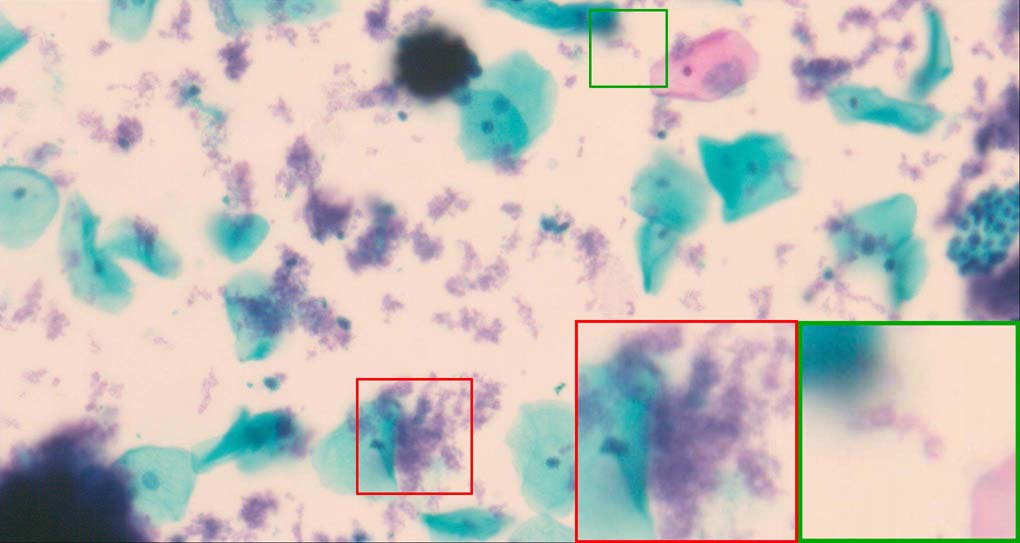

To demonstrate the effectiveness and efficiency of the proposed image fusion method , we conduct a set of comparative experiments on three image datasets. The first is composed by 8 pairs of multi-modal medical images and the second one contains 15 pairs of multi-focus gray or color natural images. These two datasets are often used in many related papers and some examples are shown in Figure 3(a) and Figure 3(b). The third one is a new multi-focus cervical cell image dataset collected by ourselves, which consists of 15 groups of color images and each group contains a series of multi-focus cervix cell images with size of or , etc. Some source examples are shown in Figure 3(c). Our source code implemented in C++ along with the new multi-focus cervical cell image dataset is available online.

Figure 9, Figure 10 and Figure 11 show the comparative fused results of the multi-focus cell images shown in Figure 3(c). For clarity, we also present a closeup view in the right-bottom of each sub-picture in Figure 9 and Figure 10. As shown in the close-up views of Figure 9, the fused images based on DSIFT, IM, MWGF and BF methods are extremely blurred in the boundary and fail to keep the details of cell nucleus. Furthermore, the DTCWT and NSCT based methods produce halo artifacts in the fused images, while GFF and CNN based methods fail to preserve the small cell nucleus. LP-SR based method nearly works fine which keeps the most of the details of the small size cells, but the integrity of the clustered large size cells is damaged. Fortunately, in our proposed method, the integrity of the clustered large size cells is preserved and most of the isolated small size cells are maintained from the original images, which demonstrates the best visual quality.

Similarly, as shown in the close-up views of Figure 10, the fused images from DSIFT, IM, MWGF and BF are blurred and lose some nucleus details, while the results from DTCWT, GFF, CNN and NSCT produce halo artifacts. LP-SR based method can keep details well but also produces halo artifacts and other noise. Our method can preserve the focused areas of different source images well without introducing any artifacts. For the example illustrated in Figure 11, the fused images generated by DSIFT, DTCWT, IM and NSCT all fail to preserve the focused areas of different source images and result in extremely blurred images. The GFF, CNN, MWGF and BF based method introduces a lot of color distortion of the nucleus regions and the obvious halo artifact. The result of LP-SR based method is close to the one of our method but introduces some odd color distortion. Again, our method produces fused image which can preserve the focused areas of different source images well without introducing any artifacts.